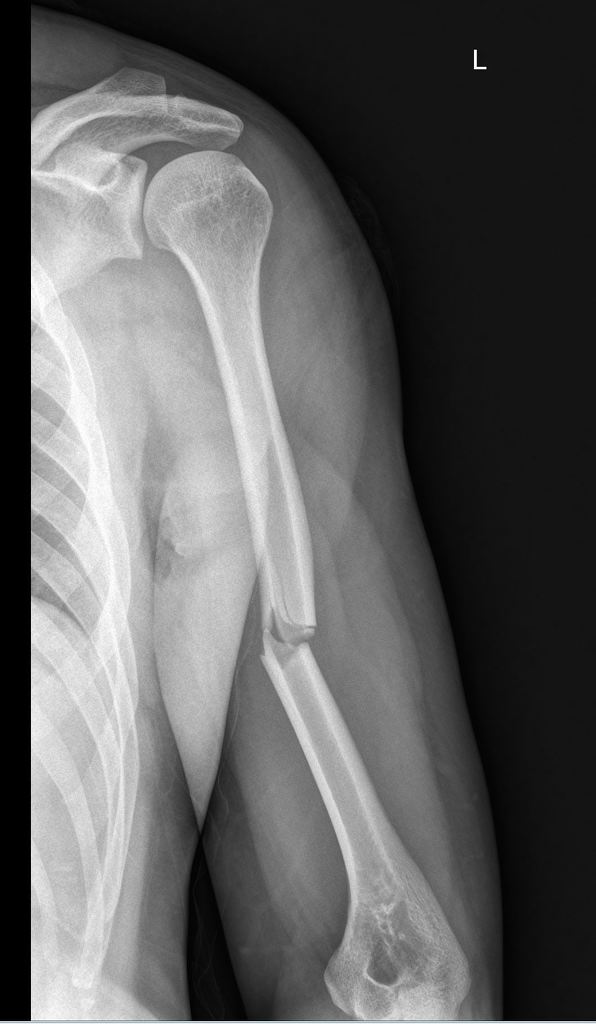

The X-ray image reveals a displaced fracture located in the middle third of the left humerus. There are no signs of dislocation in the left shoulder. On examination, the patient presented with pain and deformity in the left middle humerus, with no pain at the shoulder or elbow joints. Based on these findings, the fracture can be classified as a mid-shaft humerus fracture.

* EXAMINER: Can you interpret the X-ray image and describe the type of fracture shown for a 35-year-old male patient who presented with left arm pain after slipping and falling on a flexed elbow at work?